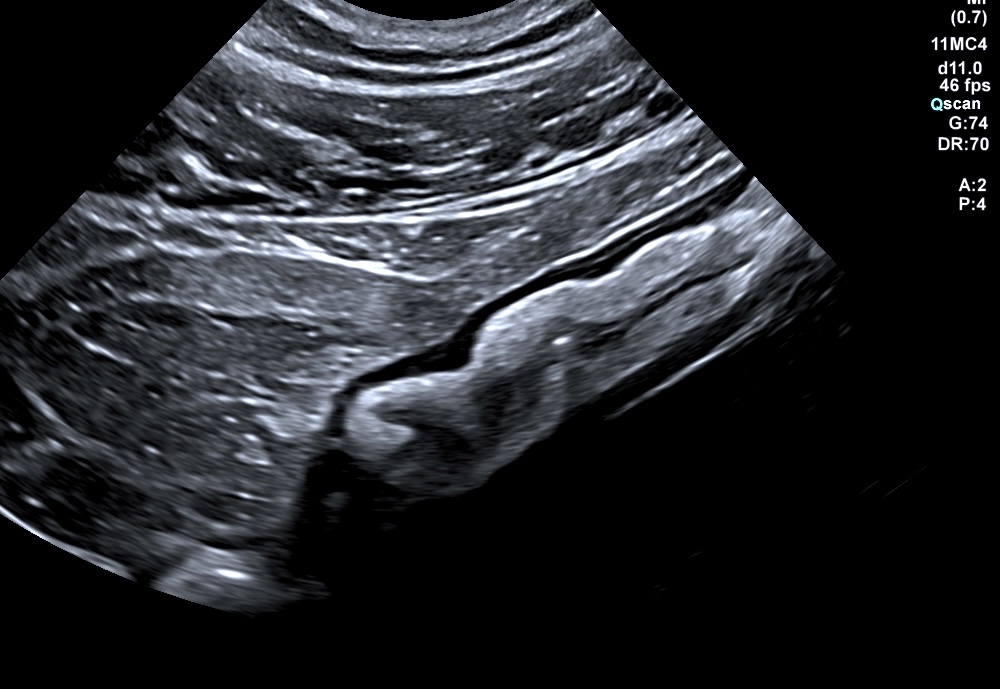

Lumière caecale distendue, avec paroi caecale fine paradoxale pour patient qui va très mal

Disparition de la structure en couches

Paroi totalement déformée, avec ulcères en surface, bord externe irrégulier, graisse infiltrée, voire épanchement liquidien

3. L'inflammation atteint la périphérie de l'anse